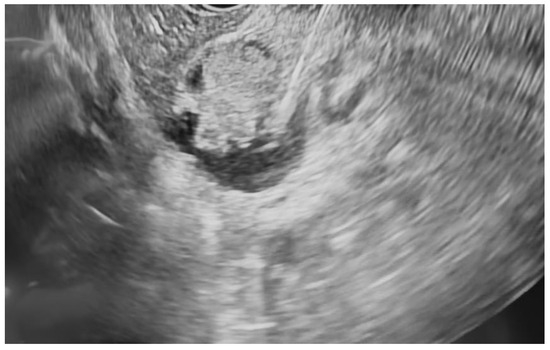

Additional notable cases in our series included a pancreatic cyst with a high-grade dysplastic nodule in an 80-year-old female patient. The initial 11.0 × 10.0 mm nodule was completely ablated (0.0 × 0.0 mm residual) after a single RFA session using a 19-gauge/7 mm needle at 50 watts of power for three applications with no complications (Figure 1, Figure 2 and Figure 3). Similarly, a 41-year-old male with a 13.5 × 8.5 mm insulinoma in the pancreatic neck who presented with multiple syncopal episodes secondary to hypoglycemia achieved complete radiologic and biochemical resolution after a single RFA session using a 19-gauge/5 mm needle at 10 watts of power for two applications (Figure 4, Figure 5 and Figure 6), with no adverse events and normalization of his insulin and glucose levels post-procedure and the resolution of his syncope.

Figure 3. The RFA of the pancreatic mural nodule shown in Figure 1 and Figure 2.